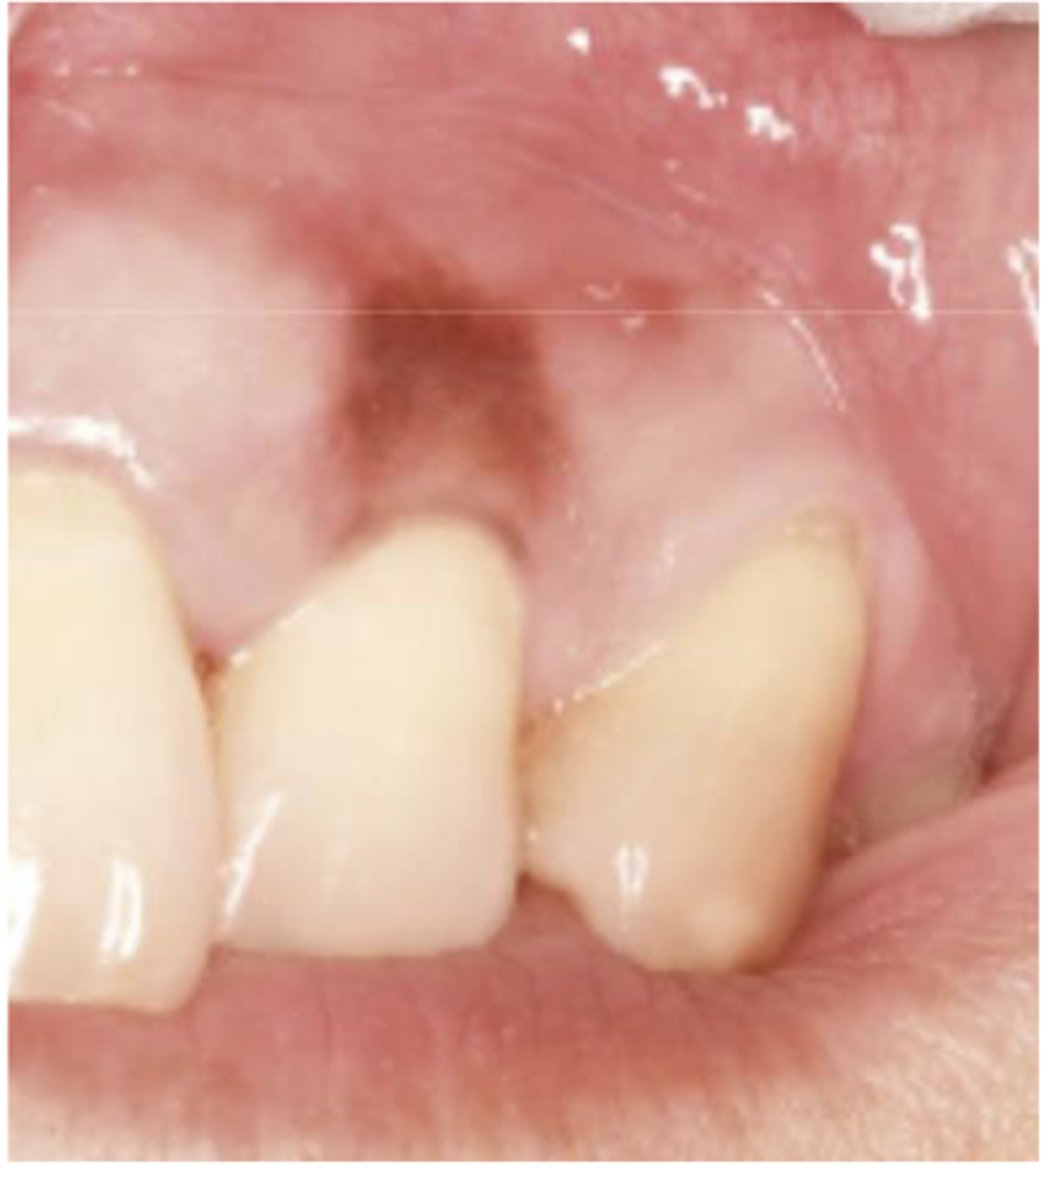

What type of pigmented lesion?

amalgam tattoo

These are clinical features of what?

- Asymptomatic, localized

- Blue-gray macule

- Localized around areas with amalgam restorations

amalgam tattoos

What is the most common location of amalgam tattoos?

gingiva/alveolar ridge mucosa (50%, then buccal mucosa, then floor of mouth)